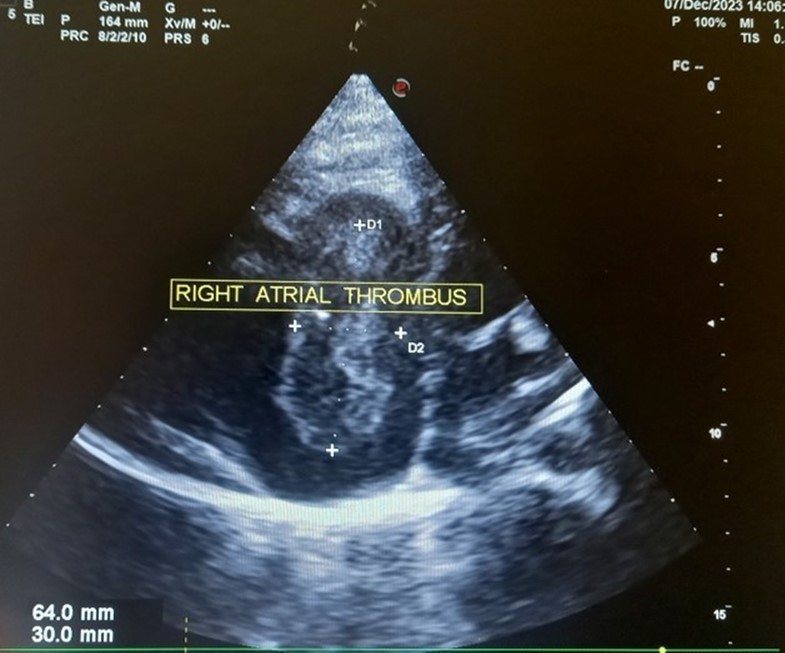

The patient underwent echocardiography (Figure 3 ) showing a low insertion of the septal and posterior leaflets of the tricuspid valve 22 mm below the tricuspid annulus, the anterior leaflet having reduced reduced mobility. Significant dilatation of the the right atrium by atrialisation of the right ventricle (RV). The rudimentary RV and its atrial stump are dilated and responsible for compression of the LV. There was no tricuspid insufficiency. No other associated congenital anomaly. However, we found a large floating thrombus in the right atrium measuring 64 mm x 30 mm in diameter. This was therefore Ebstein's disease at stage C of the Carpentier classification. The apical displacement of the tricuspid septal valve was 22 mm or 15 mm/m2). The surface area of the atrium and the atrialized right ventricle was 45 cm2 , the surface area of the right ventricle and the left cavities was 30 cm2 , the Celermajer index was calculated at 1.4 ( Grade 3).

Figure 3.Transthoracic echocardiography, apical four chambers view . Apical displacement of the tricuspid valve (a) and right atrial thrombus (b).

The ECG abnormalitie found in our patient was atrial flutter. The patients with atrial flutter may be at an increased risk of a stroke compared with the general population because during atrial flutter blood may not move as rapidly through the upper heart chambers (the atria) as it does during normal sinus rhythm. Slower movement of the blood carries the risk of formation of small blood clots that can cause a stroke. The risk of stroke is not the same for all people with atrial flutter. Therefore, some people with atrial flutter may require treatment with a blood thinner called warfarin to reduce the risk of stroke 10

In our case, the patient had, type C of EA and Grade 2. The investigation also revealed a large thrombus floating in the right atrium and no obvious regurgitation of the tricuspid valve. In addition, the septa was intact, there was no persistence of the ductus arteriosus, the pulmonary and aortic pathway were unobstructed.

Our case highlights a rare form of Ebstein's disease with a large right intra-atrial thombus. It is a rare disease discovered late in adulthood with no vicarious shunt. Echocardiography is used to establish the diagnosis and to assess its severity. Ebstein's anomaly is tricuspid valve and right ventricular malformation with variability in anatomy, pathophysiology, and clinical presentation which cannot be managed surgically in our resource-limited setting. The great anatomical heterogeneity of EA generates a wide spectrum of clinical features at presentation which cannot be managed surgically in our context of limited resources. Hence the importance of antenatal ultrasound diagnosis with a view to possible termination of pregnancy.